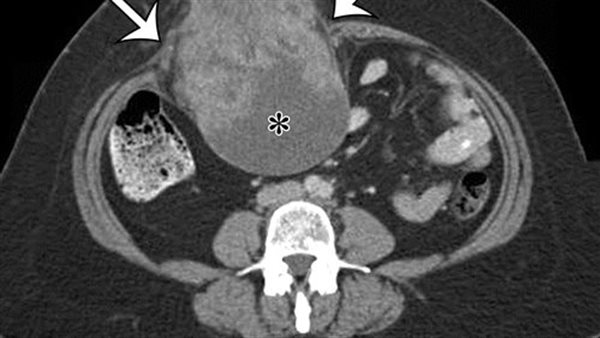

طبيعة السرطان الرخوي

سرطان الأنسجة الرخوة من أنواع السرطان النادرة، التي تبدأ على هيئة نمو للخلايا في أنسجة الجسم الرخوة، وتربط الأنسجة الرخوة بين أعضاء الجسم وتدعمها وتحيط بها، وتشمل الأنسجة الرخوة العضلات والدهون والأوعية الدموية والأعصاب والأوتار وبطانات المفاصل.